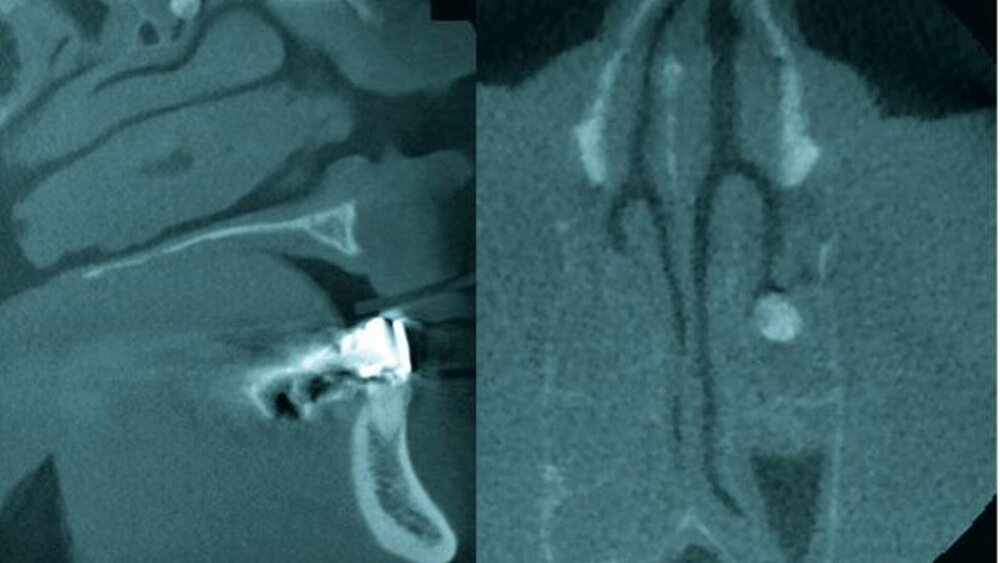

Die klinische Untersuchung (Abbildung 1) zeigte eine Bulbuselevation von rund drei Millimetern links mit gleichzeitiger Protrusio bulbi gegenüber dem rechten Bulbus oculi. Die Motilität der Augen war nicht beeinträchtigt und nicht schmerzhaft. Palpa- torisch waren die Bulbi weich und ohne Schmerzsensationen. Eine ziliare Injektion im Sinne einer inflammatorischen Reaktion lag ebenfalls nicht vor. Die periorbitale Gesichtshaut war reizlos. Subjektive Visusstörungen oder Doppelbilder wurden von der Patientin verneint. Ein Sensibilitätsdefizit im Bereich des N. supra- oder infraorbitalis lag nicht vor. Die Vorstellung der Patientin in der Augenklinik des Hauses ergab einen regelgerechten Visusbefund ohne pathologische Tonometrie. In der Computertomografie des Mittelgesichts zeigte sich ein raumfordernder, basalständiger, knochendichter Tumor der linken Orbita ohne Anhalt für einen infiltrativen Charakter (Abbildung 2).

Osteome verbleiben in aller Regel lange Zeit ohne eine klinische Symptomatik und sind häufig radiologische Zufallsbefunde, beispielsweise in Rahmen der Trauma- diagnostik. Mit der Ausdehnung der DVT-Bildgebung (digitale Volumentomografie) in der Zahnheilkunde werden solche Befunde aber zunehmend auch im Rahmen der zahnärztlichen Diagnostik erfasst und müssen dann bei der Befunderstellung auch erkannt werden. Tatsächlich stellen sie damit viel häufiger ein differenzialdiagnostisches als ein therapeutisches Problem dar.